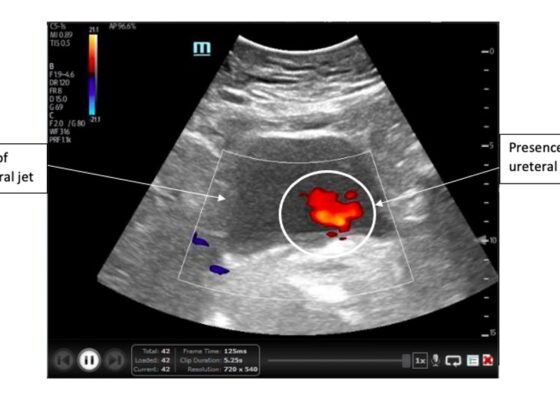

Ureteral Obstruction and Ureteral Jet Identification—A Case Report

DOI: https://doi.org/10.21980/J8206GA point-of-care ultrasound of the urinary tract was performed, evaluating the kidneys and bladder. When imaging her kidneys, right-sided hydronephrosis was noted with a normal appearance to the left kidney. To further evaluate, a curvilinear probe was placed on her bladder with color doppler to assess for ureteral jets. Ureteral jets are seen as a flurry of color ejecting from each of the ureters as urine is released from the ureterovesical junction. In a healthy patient, this finding should be seen ejecting from both ureters every 1-3 minutes as the kidneys continue to filter the blood and create urine to be stored in the bladder. In our patient, however, ureteral jets were only noted on the left side (arrow), which was significant in further verifying our suspicion of right ureteral obstruction.